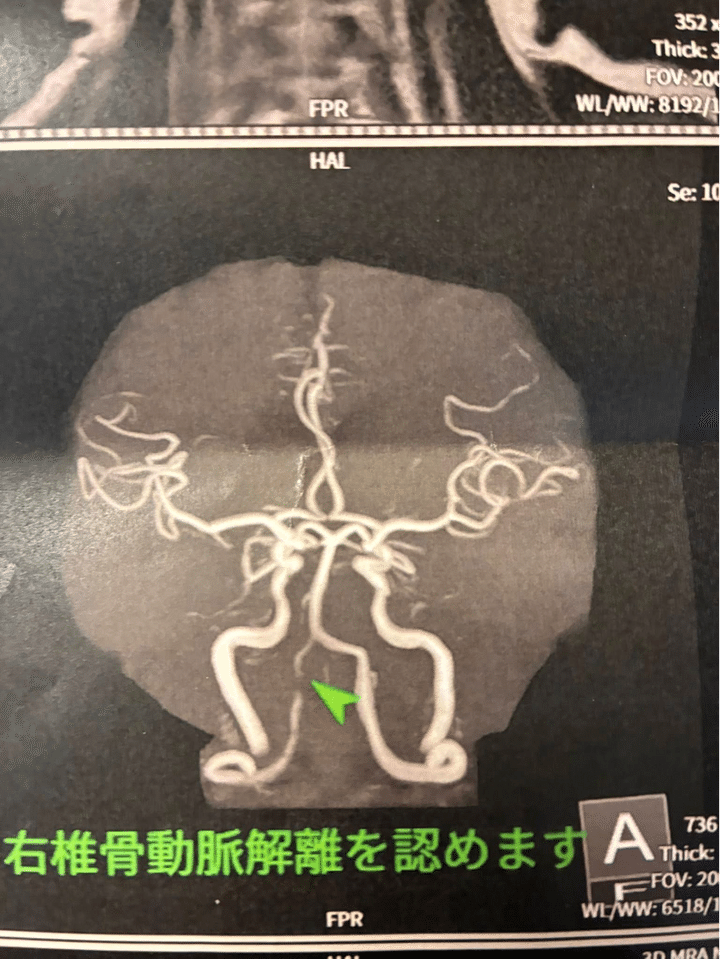

病名は、椎骨動脈解離

椎骨動脈解離

診断は、10万人に数人と言われる「椎骨動脈解離」でした。